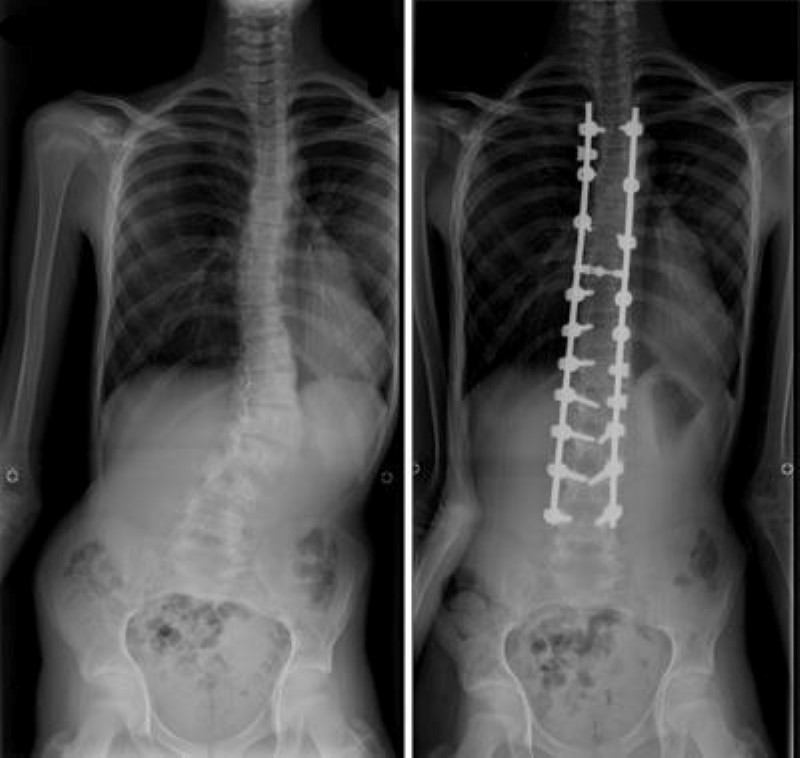

In Marfan syndrome MFS there is not enough Fibrillin in the connective tissues. These features called skeletal features happen when bones grow extra long or ligaments connective tissue that holds joints together become stretchy like loose rubber bands. Patients typically present with joint hypermobility and may have pectus carinatum or excavatum pes planus flat feet and scoliosis.

Anyone can develop spondylolisthesis but it more commonly affects people with Marfan syndrome. This disorder affects the connective tissues that are in the body. This combination of potentially weak hip joint musculature and abnormal joint shape can lead to. Anterior disc displacement with and without reduction was observed in 17 of the examined patients 810 with 4 of these patients additionally showing osteoarthrosis of the affected temporomandibular joints. They all have important functions in maintaining elasticity and strength of these tissues. Because connective tissues are so ubiquitous in the body Marfan syndrome may affect the strength support elasticity to tendons cartilage blood vessels and other parts of the body that are absolutely vita. An additional characteristic of Marfan syndrome is swelling of the membrane that surrounds the brain and spinal cord. This usually occurs in the lower spine and can cause back pain and stiffness. Dural ectasia may cause low back and leg pain abdominal pain and headaches.